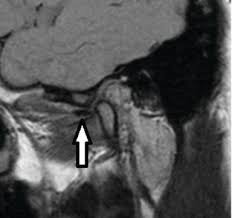

A herniated disc is sometimes also known as a slipped disc. A similar condition is a bulging disc, in which the disc fibers weaken and become stretched, but the annular covering remains intact, or doesn't break. While you are scratching your head off to slipped disc. I have been very interested in treating this area for some time now a clicky jaw in itself may not cause you a problem but it may be having a knock on effect somewhere else. Is used when the protective cartilage disk has slipped out of place inside the tmj. An mri scan is the best ways to diagnose ivdd because it shows the spine, nerves, bones and discs in detail. Slipped neck disc slipped gastric band radiology. Of course, it doesn't actually slip out.

Moreover, a slipped disc in the jaw is a relatively common disorder in those that suffer from jaw pain. They are available in distinct. This research study set out to establish whether a lowered jaw position was a 'principal factor in the tonal success of elite singers.' this recent paper is part of a long term study which aims to examine top ranking singers with more than ten years' experience. A slipped disc occurs when the gel covering a disc in the spine herniates and shifts. Even though the disc material does degenerate naturally as people age while the ligaments weaken, even a small strain or twist can cause discs to rupture. Temporomandibular jaw joint surgery temporomandibular jaw joint surgery. Is used when the protective cartilage disk has slipped out of place inside the tmj. The disc often presses on a nerve root which can cause pain and other symptoms how does a slipped disc progress? If so, we answer why and what you can do about it in our latest post. We use cookies and other technology that recognise you to improve your online experience. I have been very interested in treating this area for some time now a clicky jaw in itself may not cause you a problem but it may be having a knock on effect somewhere else. In this condition, the disc which is a jelly between two spinal bones, ruptured and may come out of the spine. A herniated disc is sometimes also known as a slipped disc.

Put up on the site are deft in metalworking activities and can significantly make jobs easier for you. A slipped disc refers to an intervertebral disc of the spine that has lost its normal shape and/or consistency. Slipped neck disc slipped gastric band radiology. When your jaw closes, the disc will silently slip out of place again. In this condition, the disc which is a jelly between two spinal bones, ruptured and may come out of the spine. We use cookies and other technology that recognise you to improve your online experience. The altered shape occurs when the disc's soft inner material (nucleus pulposus) bulges or leaks out of its external fibrous covering (annulus fibrosus).1 several medical terms, such as. Diagnosis of an internal derangement or slipped disc in the jaw is based on patient presentation, history, familial history, and precise jaw joint and neck examination.

The altered shape occurs when the disc's soft inner material (nucleus pulposus) bulges or leaks out of its external fibrous covering (annulus fibrosus).1 several medical terms, such as. This means that rather than the disc, the joint is putting pressure on the soft tissue that. Mri scanners are very large. Of course, it doesn't actually slip out. Your doctor may diagnose your pain as a bulging disc, herniated disc, ruptured disc, or even slipped disc. Can further bouts of back pain be prevented? The pain that comes from a slipped disc in the jaw or associated muscle spasms can range from annoying to debilitating. Know more about slip disc treatment without spine surgery at qi spine now! A slipped disc (also called a prolapsed or herniated disc) can cause Patient got releaved from slip disc and radiating pain by #chiropractor sessions, his back pain and #pinchnerve resolved. This research study set out to establish whether a lowered jaw position was a 'principal factor in the tonal success of elite singers.' this recent paper is part of a long term study which aims to examine top ranking singers with more than ten years' experience. Patients may also be offered physiotherapy to loosen the back muscles. Slipped discs can be caused by a strain or an injury.